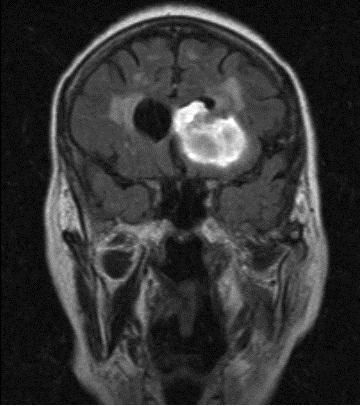

Brain scanBrain stem death is a syndrome diagnosed by a specified series of bedside tests performed by specially qualified doctors at some time convenient to them and others involved in the care of comatose patients whose brain damage appears to be mortal. It is obviously a different state from that long recognized as death. How, then, has this syndrome become accepted by some of this country’s medical profession – we don’t know how many – as equivalent to death? For those who equate it with human death but object to the notion that there can be more than one kind of death, it is death.